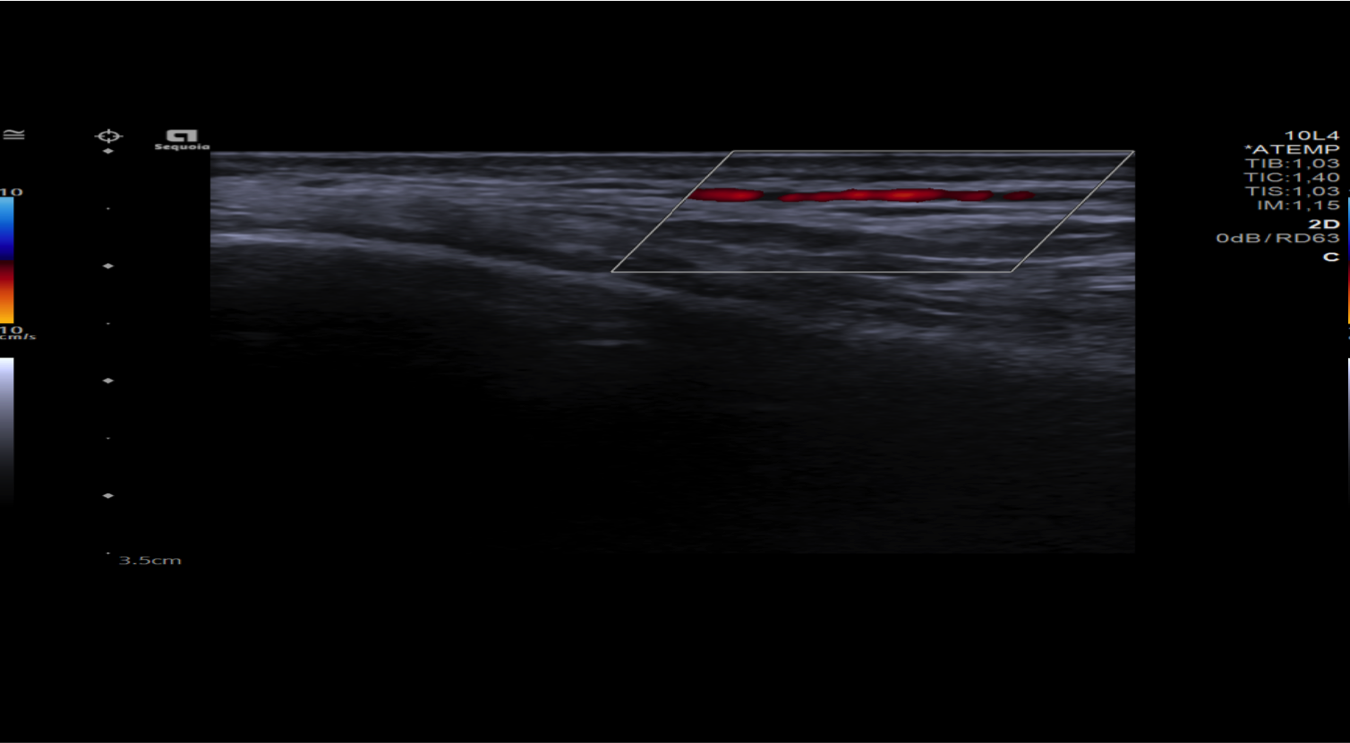

Realizamos una ecografía centrada en la zona temporal derecha del paciente.

Hallazgos ecográficos

Observamos engrosamiento parietal de arteria temporal iderecha con halo hipoecoico periférico, disminución de su calibre y cambios inflamatorios asociados.

El paciente ingresó a cargo de Neurología donde solicitaron ecografía modo Doppler de ambas arterias temporales y RMN cerebral. Además, fue valorado por Oftalmología.

En conclusión, ante un paciente de edad avanzada y síntomas que hagan sospechar la presencia de una arteritis de la temporal debe considerarse la realización de una ecografía modo Doppler para su diagnóstico y así evitar el retraso del diagnóstico definitivo mediante biopsia.